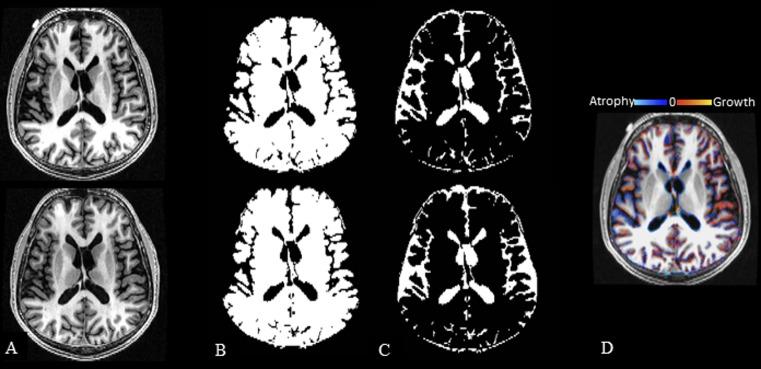

使用多种自动化分割管道,在多发性硬化症中使用 3T MRI 进行长达 5 年的全脑和深部灰质萎缩检测。

Whole brain and deep gray matter atrophy detection over 5 years with 3T MRI in multiple sclerosis using a variety of automated segmentation pipelines.

Cerebral atrophy is common in multiple sclerosis (MS) and selectively involves gray matter (GM). Several fully automated methods are available to measure whole brain and regional deep GM (DGM) atrophy from MRI.

To assess the sensitivity of fully automated MRI segmentation pipelines in detecting brain atrophy in patients with relapsing-remitting (RR) MS and normal controls (NC) over five years.

Consistent 3D T1-weighted sequences were performed on a 3T GE unit in 16 mildly disabled patients with RRMS and 16 age-matched NC at baseline and five years. All patients received disease-modifying immunotherapy on-study. Images were applied to two pipelines to assess whole brain atrophy [brain parenchymal fraction (BPF) from SPM12; percentage brain volume change (PBVC) from SIENA] and two other pipelines (FSL-FIRST; FreeSurfer) to assess DGM atrophy (thalamus, caudate, globus pallidus, putamen). MRI change was compared by two sample t-tests. Expanded Disability Status Scale (EDSS) and timed 25-foot walk (T25FW) change was compared by repeated measures proportional odds models.

Using FreeSurfer, the MS group had a ~10-fold acceleration in on-study volume loss than NC in the caudate (mean decrease 0.51 vs. 0.05 ml, p = 0.022). In contrast, caudate atrophy was not detected by FSL-FIRST (mean decrease 0.21 vs. 0.12 ml, p = 0.53). None of the other pipelines showed any difference in volume loss between groups, for whole brain or regional DGM atrophy (all p>0.38). The MS group showed on-study stability on EDSS (p = 0.47) but slight worsening of T25FW (p = 0.054).

In this real-world cohort of mildly disabled treated patients with RRMS, we identified ongoing atrophy of the caudate nucleus over five years, despite the lack of any significant whole brain atrophy, compared to healthy controls. The detectability of caudate atrophy was dependent on the MRI segmentation pipeline employed. These findings underscore the increased sensitivity gained when assessing DGM atrophy in monitoring MS.